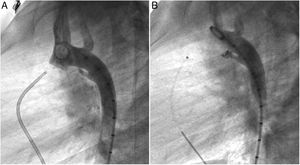

Both patients with history of previous PDA closure were successfully treated. The first was a seven year-old child who had a coil implanted at age three. The procedure was technically difficult, requiring a guidewire capture using a snare catheter to go through the residual PDA (Figure 11), and an Amplatzer duct occluder II 3x4 mm device was implanted successfully. The second patient was a 19 month-old child with PDA and pulmonary hypertension after an unsuccessful surgical ligation. In this case, sizing with a Tyshak balloon was required before implanting an Amplatzer duct occluder II 3x4 mm device (Figure 12).

A coil was used in 139 patients (62.9%) and an Amplatzer duct occluder was used in 79 patients (35.7%). In the three remaining patients (1.4%), an Amplatzer vascular plug was used for closure (Figures 2-8). Despite the higher overall rate of coil device implantation, Amplatzer duct occluder usage had been clearly superior since 2011. Of all coil devices used, 55% were either 4x4 mm or 5x4 mm in size (Figure 9), and of all duct occluder devices used, 72% were Amplatzer duct occluder I 6x4 mm or 8x6 mm in size (Figure 10), which correlates to the fact that most patients who were referred had small- to moderate-sized ductus arteriosus. While ADO II and ADO II AS devices can be implanted in a retrograde fashion, only on two occasions was a retrograde deployment performed (both ADO II devices).